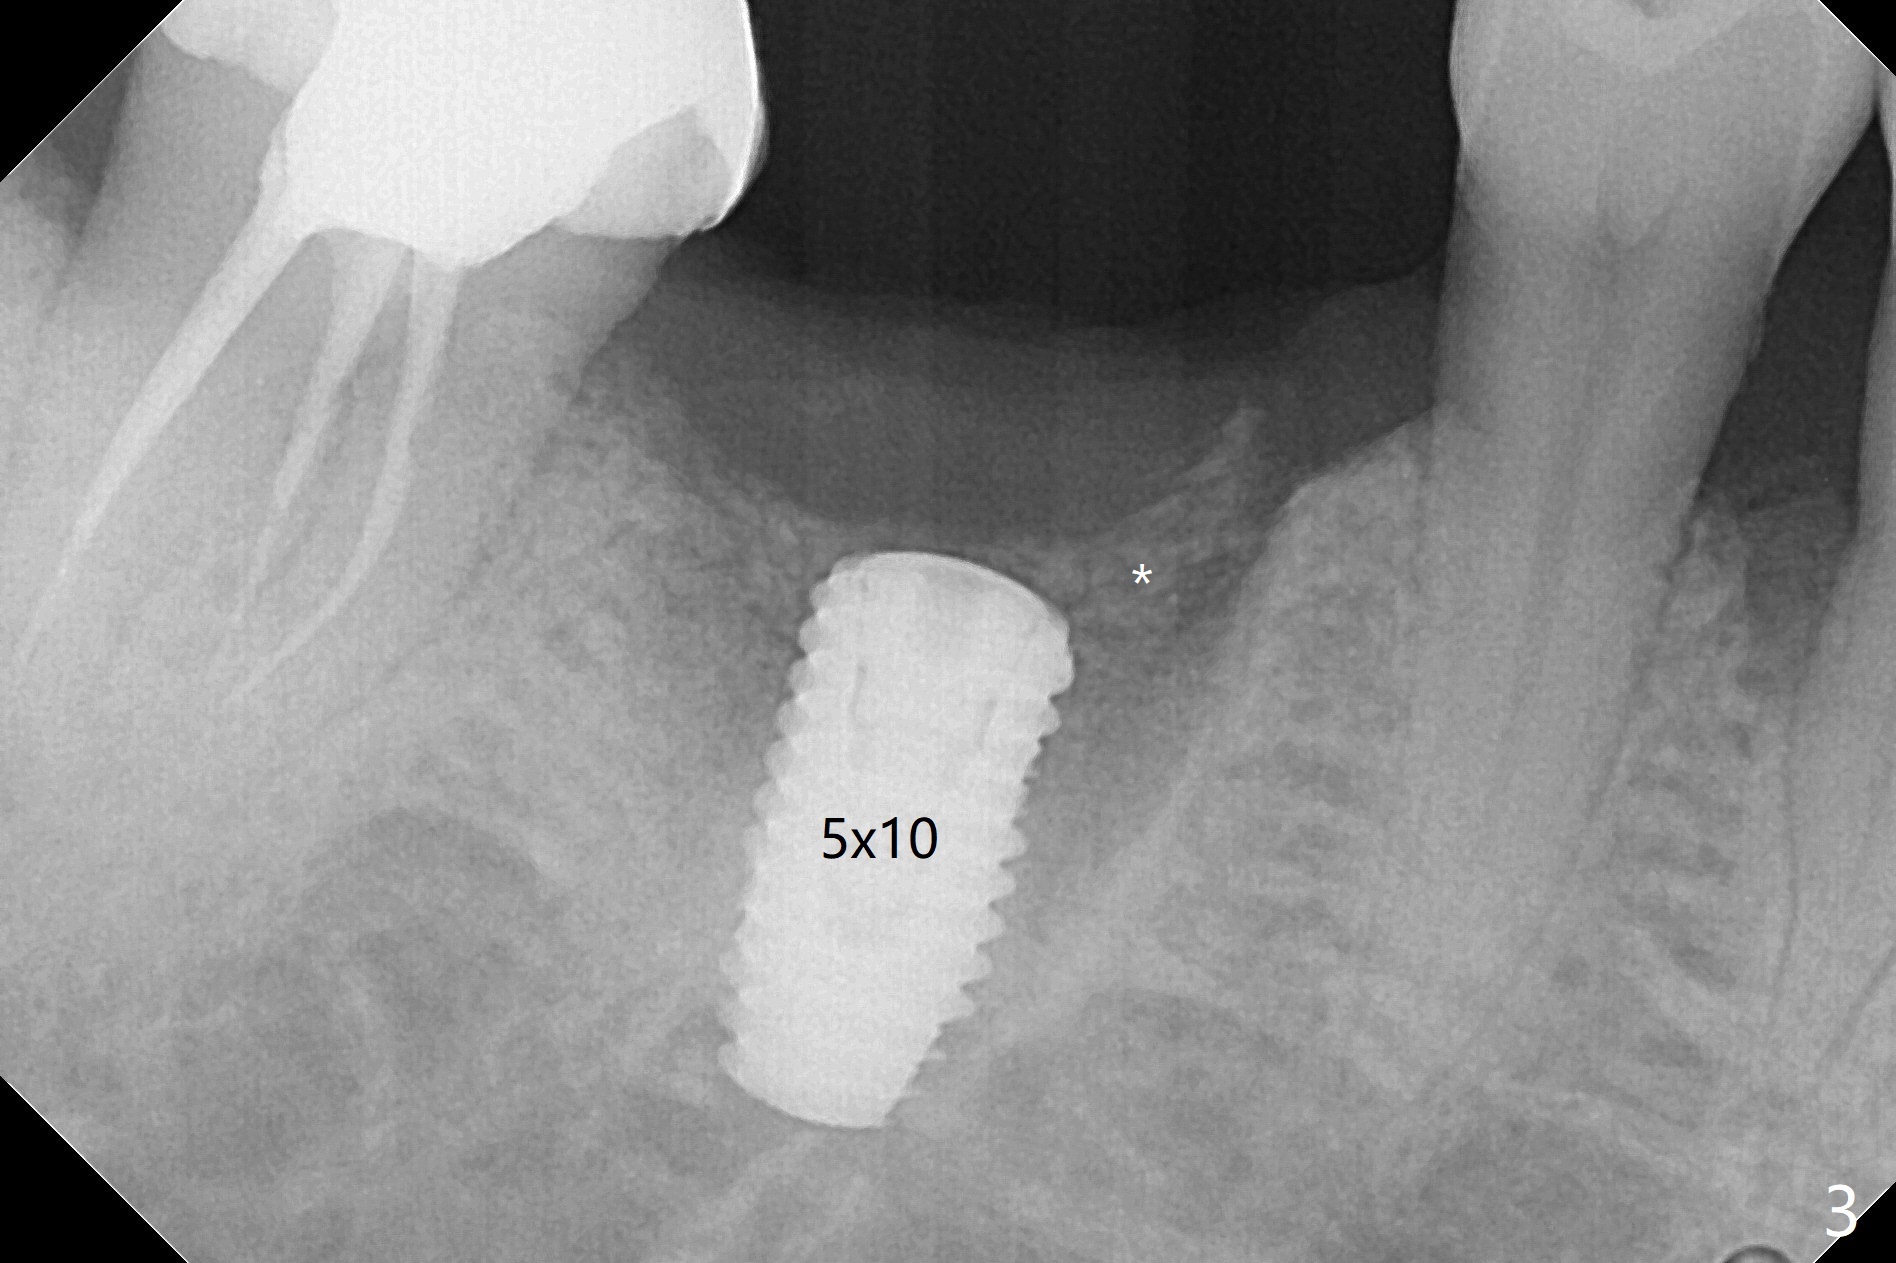

The sockets of #30 (M) of a smoker (M) are apparently not healing ~ 2 months post extraction (Fig.0, 0'). The ridge looks wide 3 months post extraction without bone graft in other office before (Fig.1) and after (Fig.2) flap surgery. The socket appears to have healed perfectly consi-dering buccal defect (M) revealed by CT ~ 1 month earlier. When a 5x10 mm implant is placed with guide and high torque (in spite of overprep), granu-lation tissue is found mesio-buccal (MB, Fig.2 *). After curettage, bone graft is placed around the implant, especially MB (Fig.3 *), followed by PRF. Periodontal dressing dislodged a few days postop because of mastication on the right side (Fig.4), whereas the anterior one (24/26) remains in place. There is a small gap around the implant when it is uncovered (Fig.5 arrowheads). It appears that some of bone graft gets lost from the incision (smoker). A 6.5x5.5(4) mm cemented abutment is seated and torqued at 30 Ncm before impression (Fig.6). There is no bone loss 11 months post cementation (Fig.7).